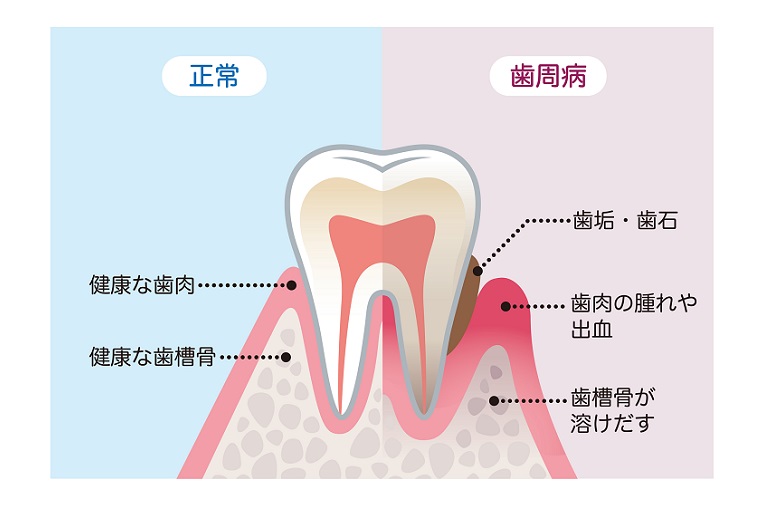

歯周病

歯周病は「歯周病菌」が歯肉の炎症を引き起こし、腫れや出血を伴ったり、さらに進行すると歯が抜けてしまう怖い病気です。

歯周病は「歯周病菌」が歯肉の炎症を引き起こし、腫れや出血を伴ったり、さらに進行すると歯が抜けてしまう怖い病気です。